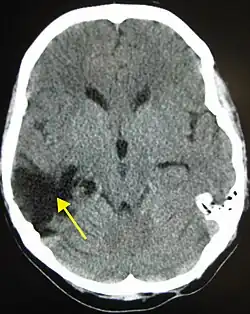

CT scan showing cerebral contusions, hemorrhage within the hemispheres, and subdural hematoma. There is also displaced skull fracture of left transverse parietal and temporal bones.[2]

CT scan showing spread of the subdural hematoma (single arrows), midline shift (double arrows)

Systems also exist to classify TBI by its pathological features.[20] Lesions can be extra-axial, (occurring within the skull but outside of the brain) or intra-axial (occurring within the brain tissue).[24] Damage from TBI can be focal or diffuse, confined to specific areas or distributed in a more general manner, respectively;[25] however, it is common for both types of injury to exist in a given case.[25]

Hematomas, also focal lesions, are collections of blood in or around the brain that can result from hemorrhage.[11] Intracerebral hemorrhage, with bleeding in the brain tissue itself, is an intra-axial lesion. Extra-axial lesions include epidural hematoma, subdural hematoma, subarachnoid hemorrhage, and intraventricular hemorrhage.[38] Epidural hematoma involves bleeding into the area between the skull and the dura mater, the outermost of the three membranes surrounding the brain.[11] In subdural hematoma, bleeding occurs between the dura and the arachnoid mater.[23] Subarachnoid hemorrhage involves bleeding into the space between the arachnoid membrane and the pia mater.[23] Intraventricular hemorrhage occurs when there is bleeding in the ventricles.[38]